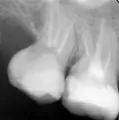

За день до события ел довольно твердые орехи, миндаль, 1 штуку (потом решил запить водой), но после них вечером и утром ел салаты, как обычно, и все нормально. После того как утром ел тонкий бездрожжевой армянский лаваш, который за 1 день стал немного черствым (корочка чуть тверже чем чипсы), в момент надкусывания дальними зубами услышал хруст и совсем небольшой кусочек зуба обнаружил в еде. По не понятной пока причине появилась трещина стенки 7-го зуба со стороны языка в четверти стенки, которая ближе к горлу. Видно, что есть трещина и в месте трещины есть небольшое углубление цвета кофейного налета (предположительно оттуда и выпал кусочек).

Стеночка еще держится, но упирается в десну и шатается.

Стенку зуба, конечно, необходимо только удалить, а восстановить коронковую часть зуба теперь можно будет только вкладкой и коронкой.